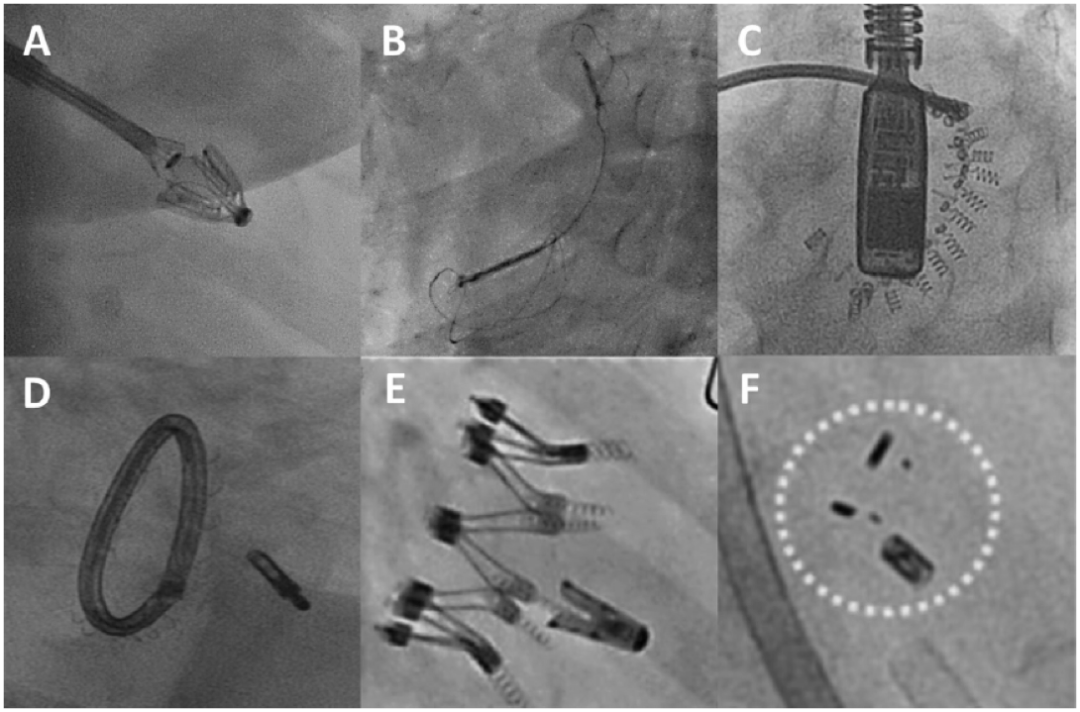

除MitraClip外,还有大量二尖瓣修复装置处于不同的开发阶段和监管批准阶段。这些器械通常处理外科修复过程的一个方面,无论是瓣环成形术、瓣叶或腱索修复,然而已经开展了组合修复手术(图7和图8)。虽然这个列表并不详尽,但它包括了主要的竞争者,重点是技术和可用的临床结果(图9)。

ero为什么不显示经导管二尖瓣修复术:相关病理生理学、研究和治疗综述_https://www.jmylbn.com_新闻资讯_第9张

图7:一名80岁男性退行性二尖瓣返流患者经导管二尖瓣修复联合Amend和MitraClip装置治疗。

(A)术前彩色多普勒经食管超声心动图(TEE)显示严重MR。术中彩色多普勒经食管超声心动图(TEE)显示(B)瓣环成形术和(C)缘到缘修复术后MR显著降低。(D)透视显示Amend和MitraClip均已就位。

MR:二尖瓣返流;TEE:经食管超声心动图。

ero为什么不显示经导管二尖瓣修复术:相关病理生理学、研究和治疗综述_https://www.jmylbn.com_新闻资讯_第10张

图8:一名68岁男性患者使用Amend和NeoChord装置进行经导管二尖瓣修复。

(A)术前经食道彩色多普勒超声心动图显示严重二尖瓣返流。术中经食管彩色多普勒超声心动图显示(B)瓣环成形术和(C)腱索修复术后二尖瓣返流显著减少。LA:左心房;LV:左心室。

图10:经导管二尖瓣修复器械的透视图像。(A)Pascal。(B)Carillon。(C) Cardioband;(D)Amend与MitraClip联合使用。(E) IRIS与与MitraClip联合使用;(F) Mitrallign;